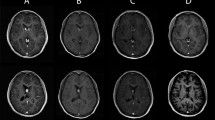

The detection of SEGAs is currently possible using several imaging methods, such as CT or MRI and ultrasound, from the neonatal period or even during gestation [4]. CT or MRI examinations have revealed that almost all SEGAs are located in the vicinity of the foramen of Monro, while some reported that it could also occur in the third ventricles. On CT, the tumors appear as uniform-density masses and high-density calcification in the perimeter of masses. MRI represents the main diagnostic modality for SEGAs. On MRI, the tumors show iso- or hypointensity on T1WI and iso- or hyperintensity on T2WI [4, 16]. Punctuate or nodular calcifications are common in the border of the tumors, while small cystic changes in the tumors are rare [16]. After the injection of contrast agent, the tumors markedly show homogeneous or heterogeneous enhancement. With CT and MRI, together with the specific tumor location, the preliminary diagnosis of SEGAs can be considered (Fig. 1).